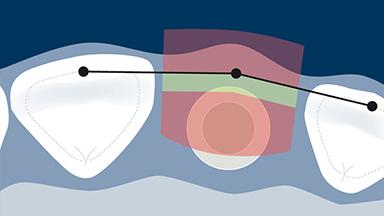

However, the same level of outcome has not been achieved in this case, where significant recession of the facial mucosa has exposed the underlying abutment, resulting in an unesthetic asymmetry.

In the event of esthetic complications, management may include a prosthodontic or surgical approach, and some cases will require both. It is important to base this management on correct diagnosis of the type of complication and its etiology.

- describe how implant positioning can lead to esthetic complications